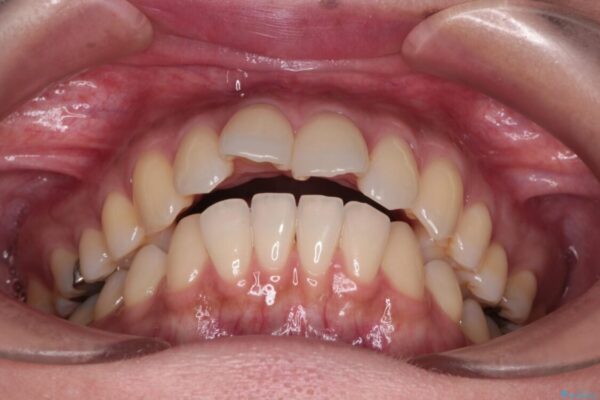

上の前歯の突出感を気にして来院された患者様です。

目立たない装置を希望とのことで、上顎左右第一小臼歯を抜歯し、インビザラインにて矯正治療を行うこととしました。

治療前

• 上顎前歯の突出を軽減 インビザラインによる抜歯矯正 治療前画像